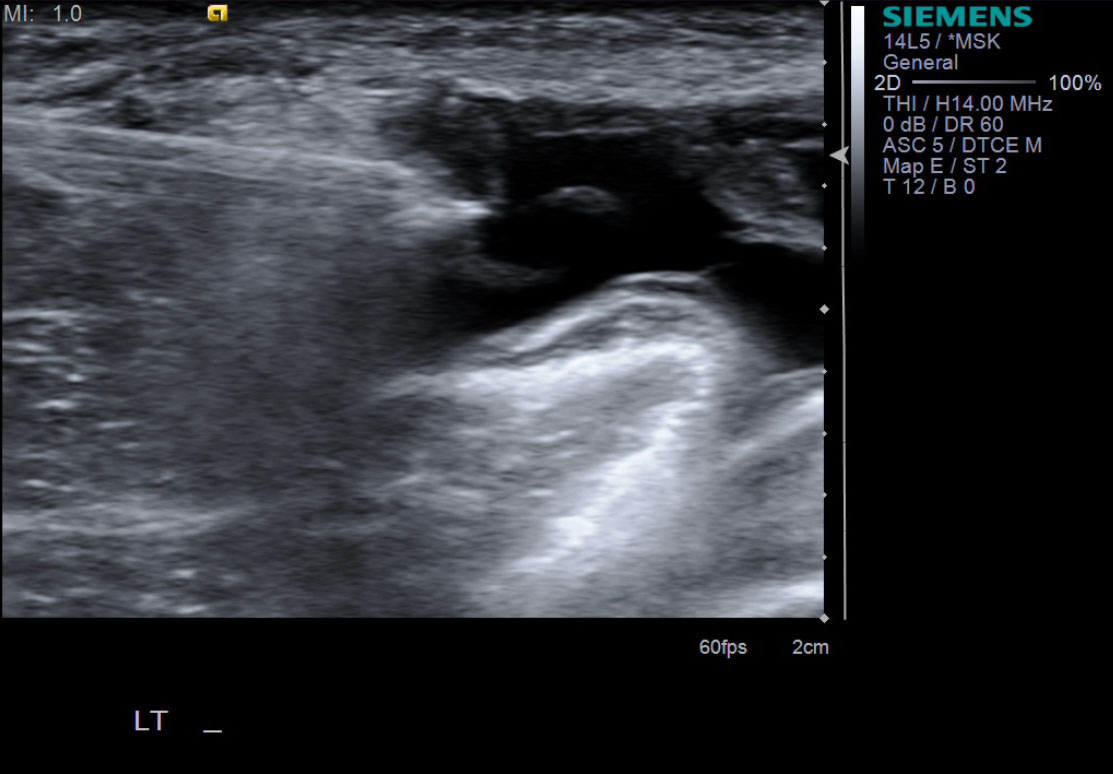

11. Place the 10cc syringe on the end of the 18g needle.

12. While watching under ultrasound, aspirate almost the entirety of the Baker's cyst. Often the fluid is thick and gelatinous. Therefore, spinning the needle or bobbing it back and forth may help aspirate the majority of the fluid.

• descriptiondescription

13. Exchange the 10cc syringe containing the aspirated fluid, with the 3cc syringe containing the steroid/anesthetic concoction listed in step 7. Inject the 3cc's into the cyst cavity.